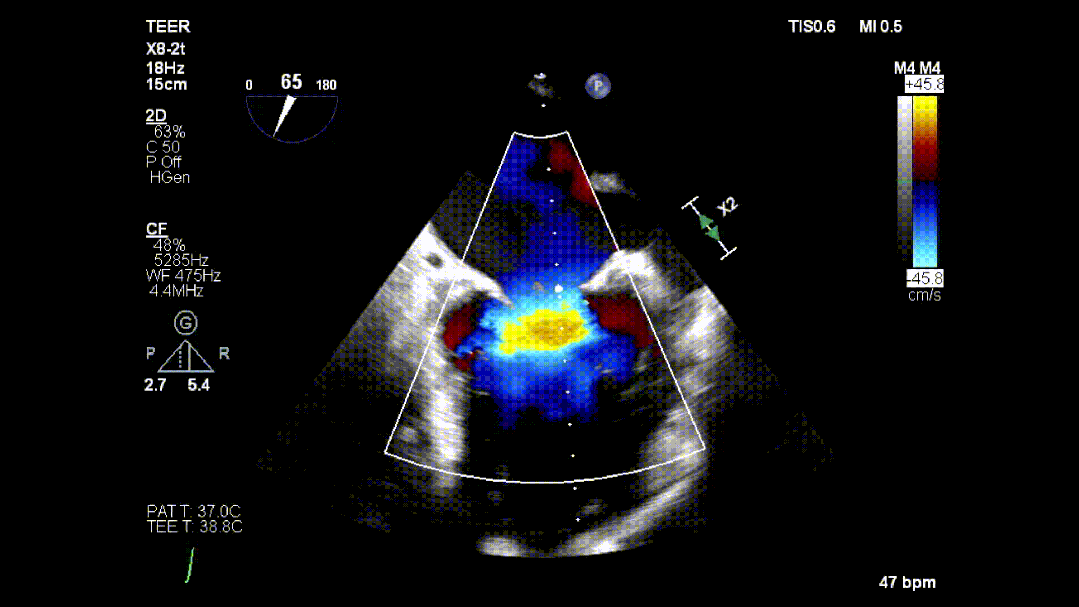

本次培训的“重头戏”—— 两台高难度 TEER 手术沉浸式观摩,将培训氛围推向高潮。手术病例分别为 “P2 宽大脱垂病变” 与 “早期 Barlow 病变”,由厦门大学心血管病医院团队与浙江大学附属邵逸夫医院团队协同完成。术中,专家团队操作精准、配合默契,不仅完美展现了 TEER 技术在复杂病例中的应用优势,更通过实时讲解,让学员直观掌握手术关键步骤、解剖评估要点与应急处理思路。

病例1: